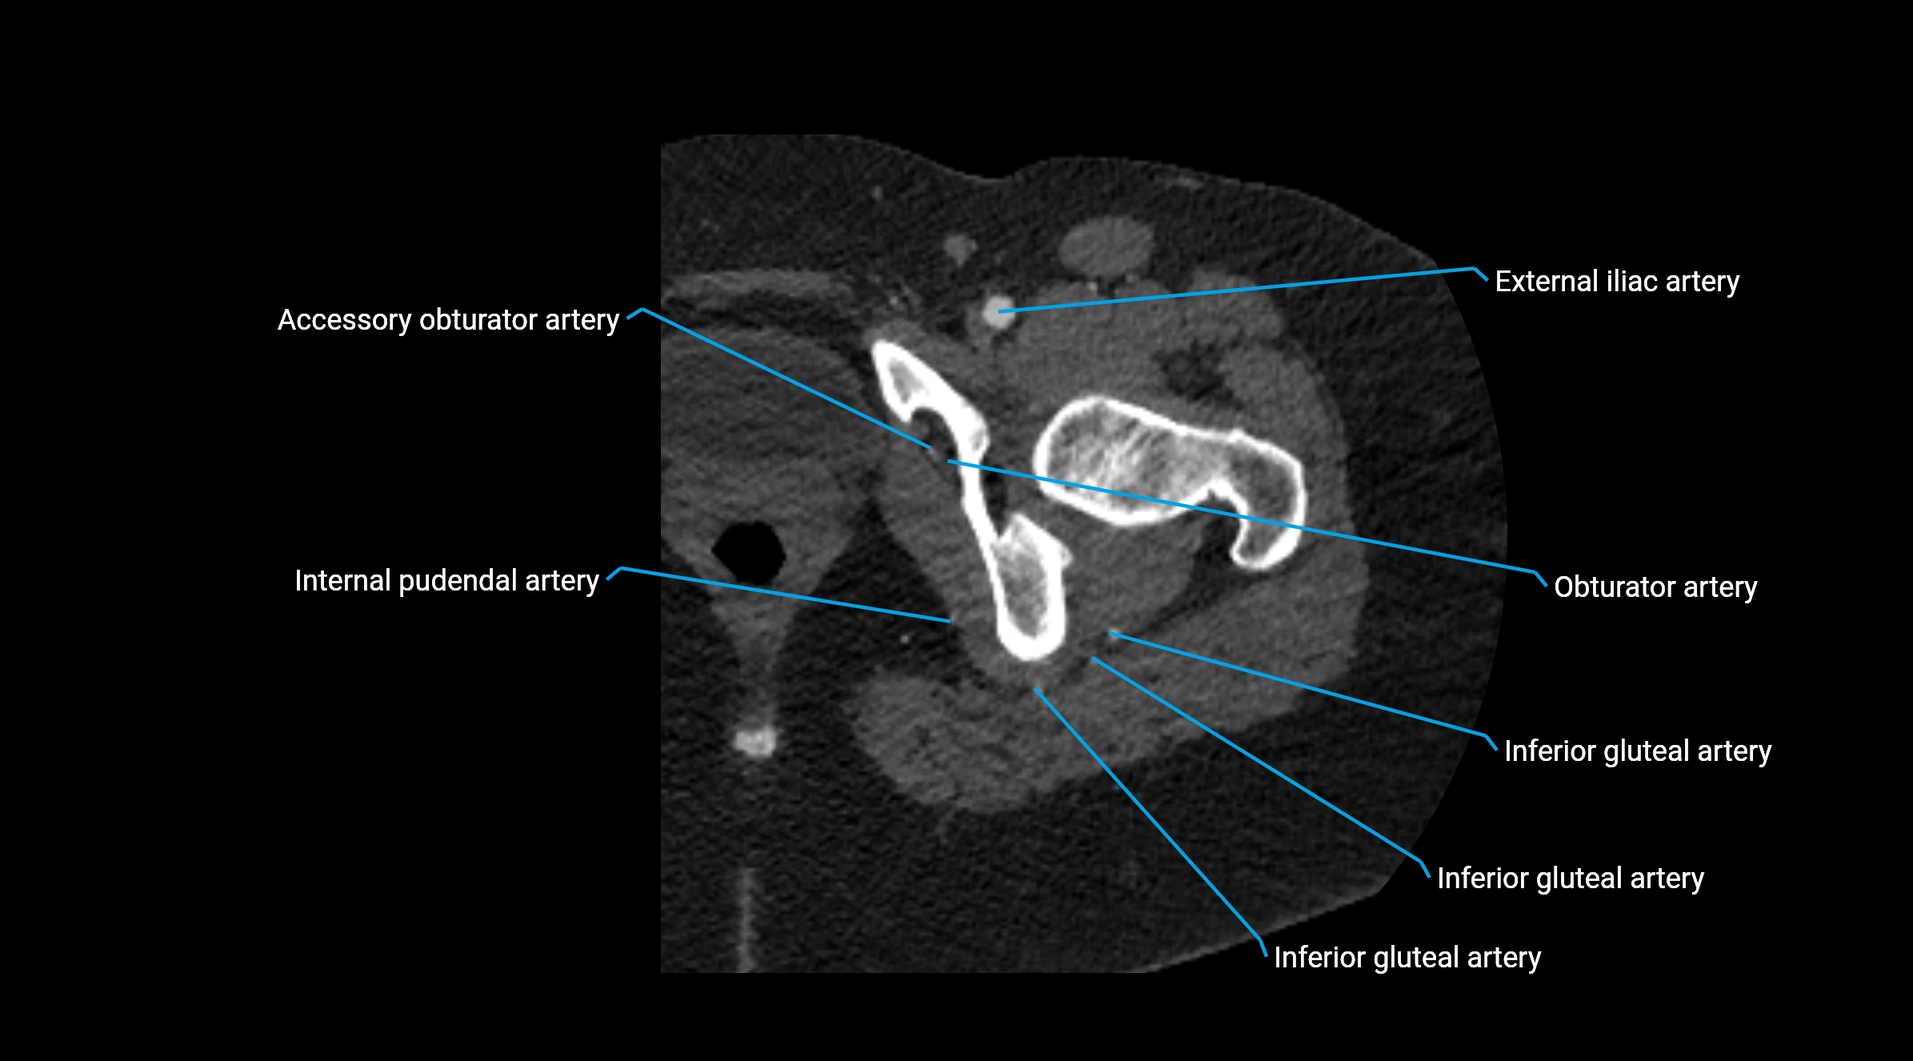

CT images

image